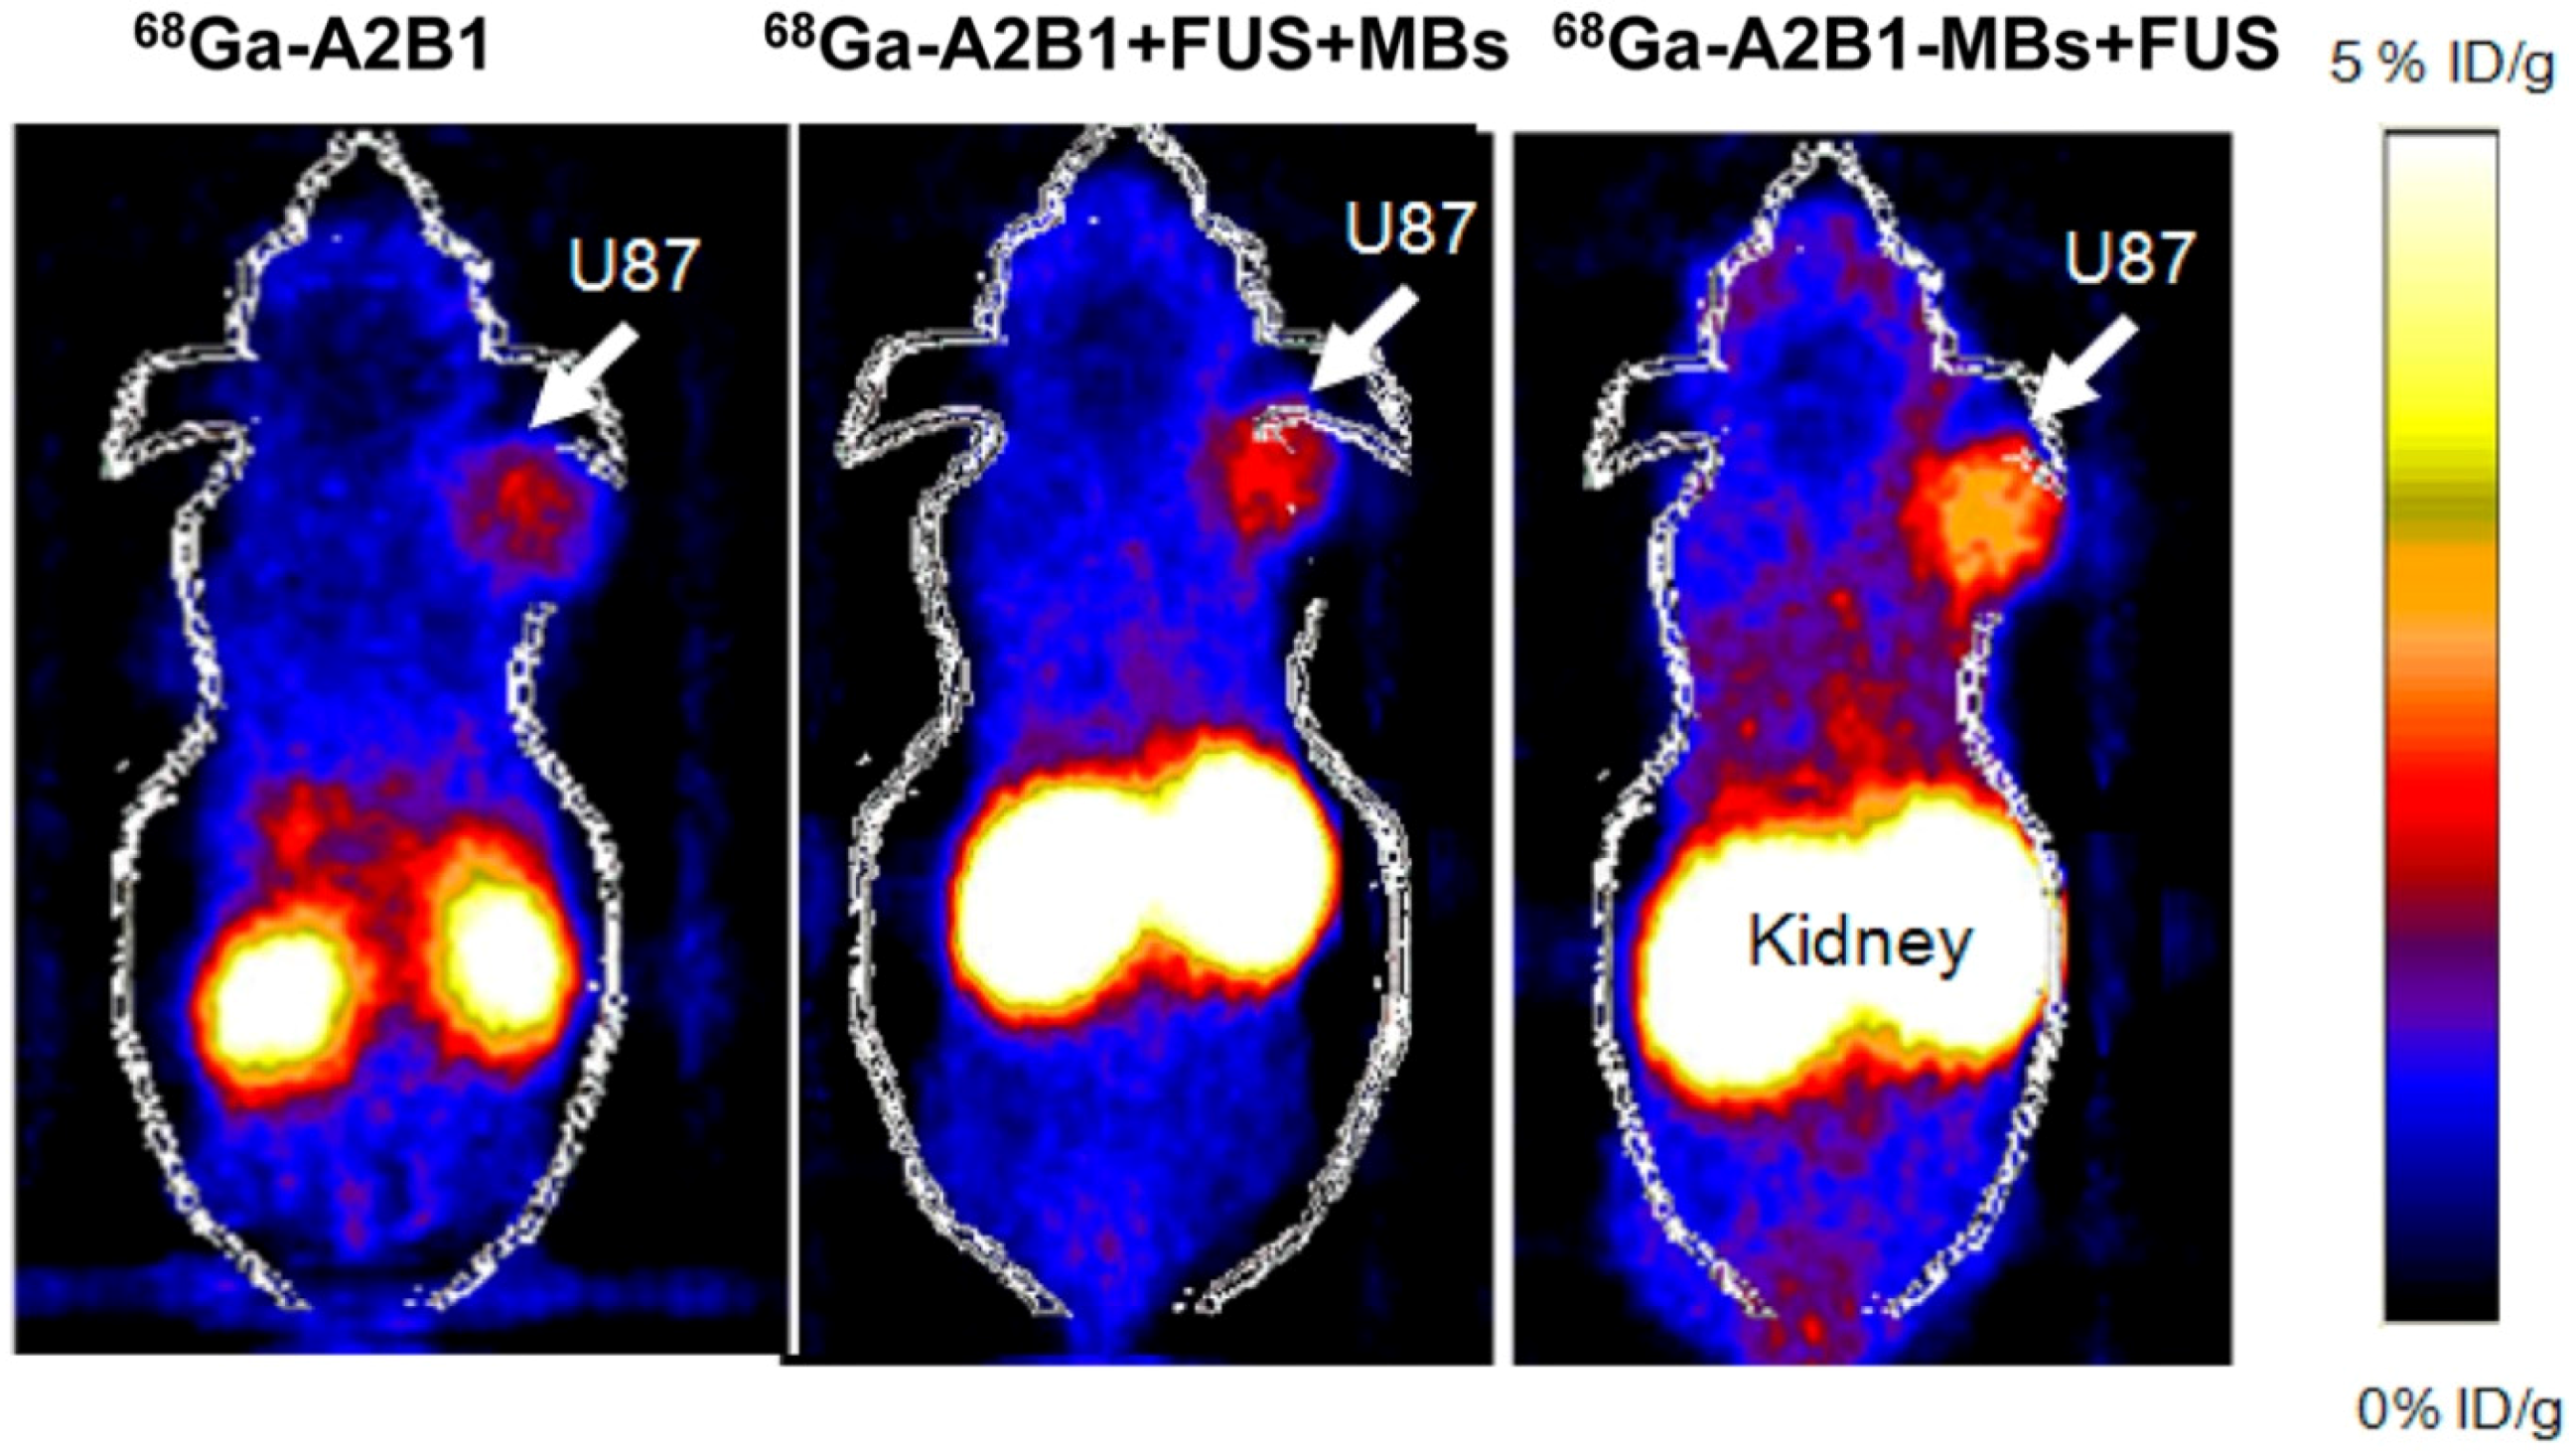

- Chung, Y.H.; Hsu, P.H.; Huang, C.W.; Hsieh, W.C.; Huang, F.T.; Chang, W.C.; Chiu, H.; Hsu, S.T.; Yen, T.C. Evaluation of prognostic integrin α2β1 PET tracer and concurrent targeting delivery using focused ultrasound for brain glioma detection. Mol. Pharm. 2014, 11, 3904–3914. [Google Scholar] [CrossRef] [PubMed]